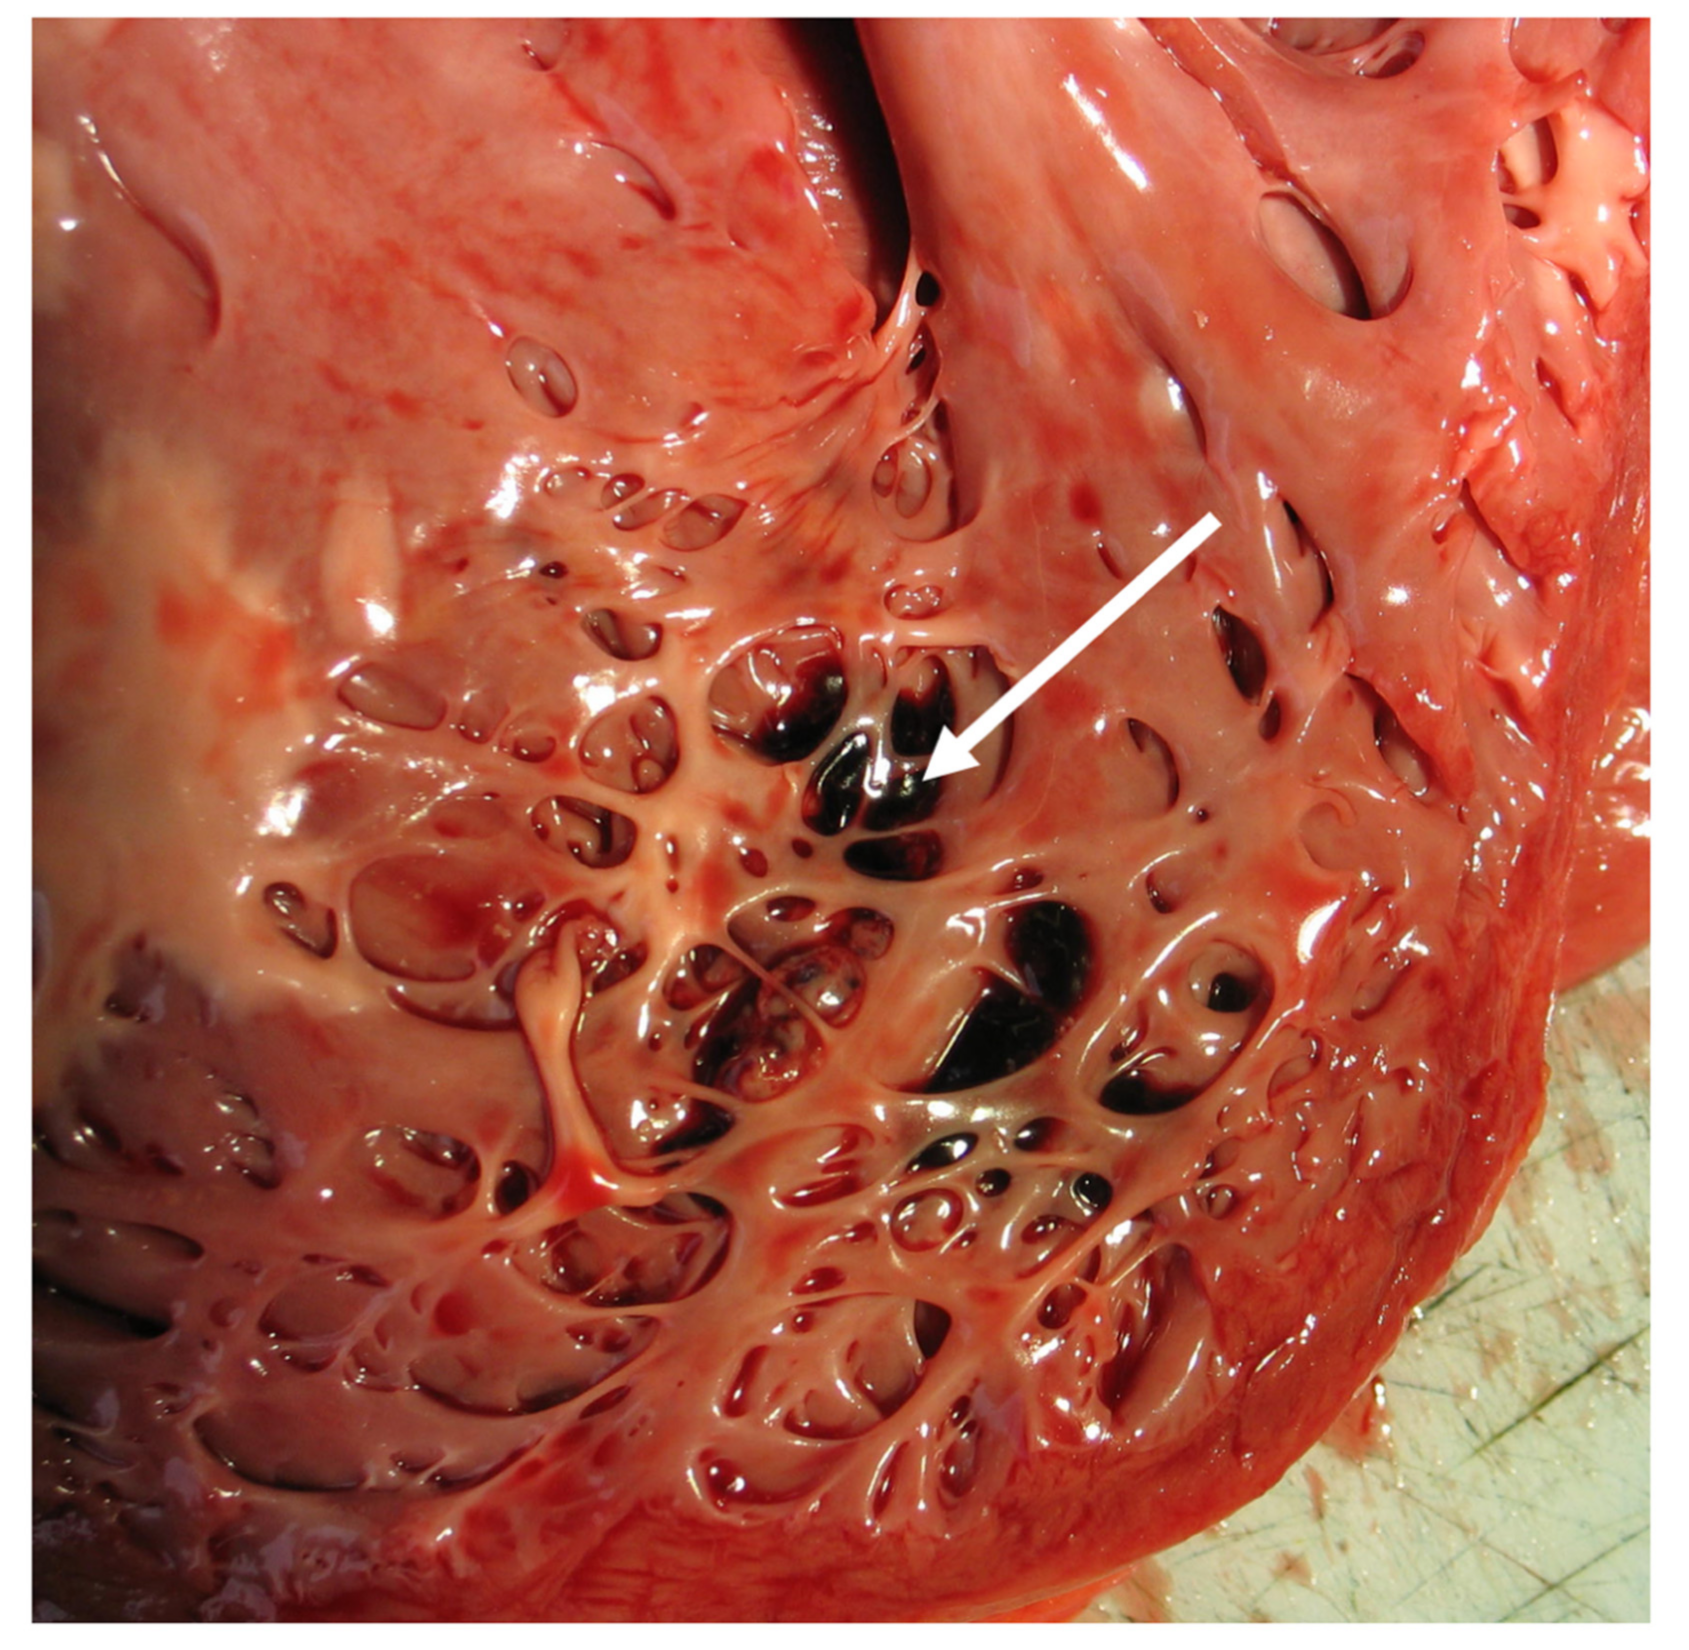

1. At least four prominent trabeculations and deep intertrabecular recesses; |

2. Blood flow between the cavity of the left ventricle and the recesses demonstrable by color Doppler echocardiography or by the use of ultrasonographic contrast medium; |

3. The left ventricular wall segments show a typical bilaminar structure, and the noncompact subendocardial layer is at least twice as thick as the compact subepicardial layer in systole; |

4. No other cardiac abnormalities present. |